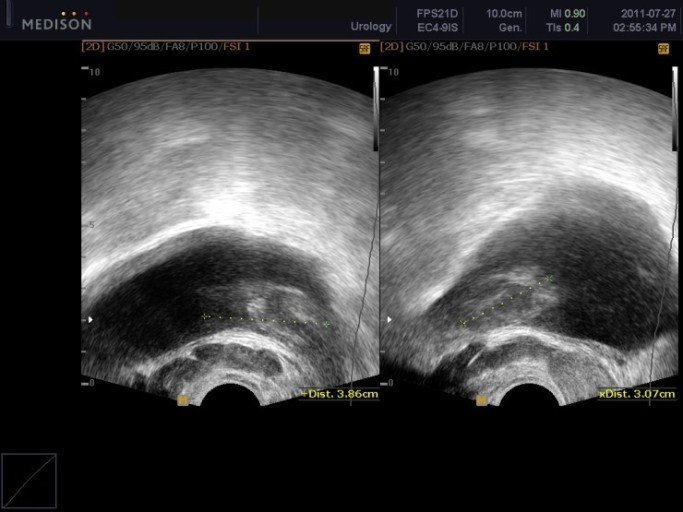

5. 요실금 및 수신증

요실금이란 자기도 모르는 사이에 소변이 나오는 증상입니다. 전립선암 초기증상으로 전립선에서 가장 가까운 방광 쪽으로 번질 그럴 때에 요실금 증상이 발생할 수도 있습니다. 또한 요관이 막히면서 소변이 방광으로 전달되지 못하고, 신장에 고이게 되는 그럴 경우를 수신증이라고 합니다.. 수신증의 그럴 경우 몸 뒤쪽인 등 부분에 고통이 생기는 것이 증상이라고 합니다.